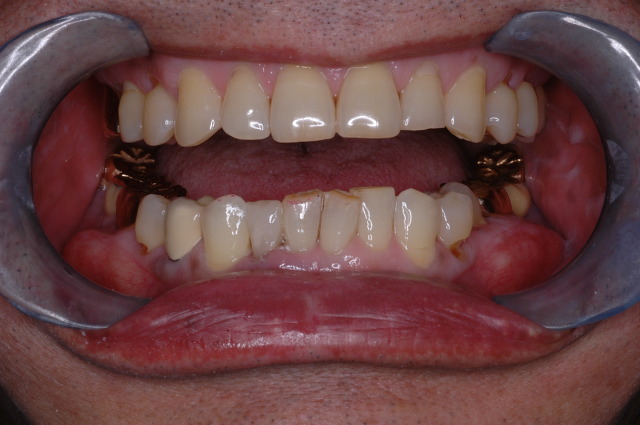

오른쪽(환자의) 부위 사진입니다.

위에는 임플란트가 식립되었고

아래는 수년전에 브릿지 치료를 받았습니다.